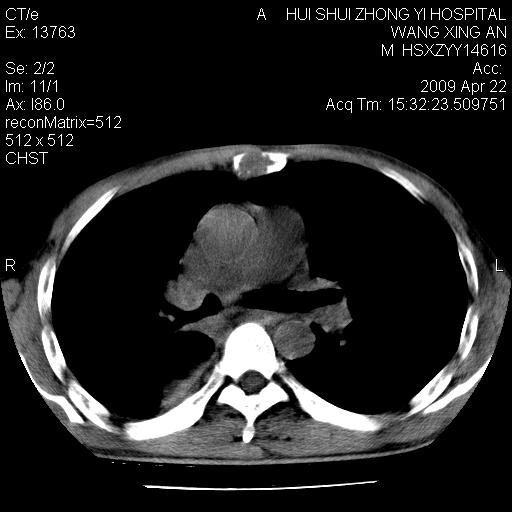

标题: CT19534:患者男、46岁咳嗽、胸痛半月。 [打印本页]

标题: CT19534:患者男、46岁咳嗽、胸痛半月。

1、右下肺中央型肺癌并右肺转移,右肺下叶不张。(肿块围绕右肺下叶支气管生长,致管腔闭塞右肺下叶不张;右肺有结节影)。

2、右侧胸腔积液。

3、右中上肺陈旧性肺结核(右肺见纤维化病灶及点状钙化)。

1)右肺中间段支气管癌并右肺下叶肺不张。2)右肺上叶、两肺下叶背段感染性病变。3)右侧少量胸腔积液。